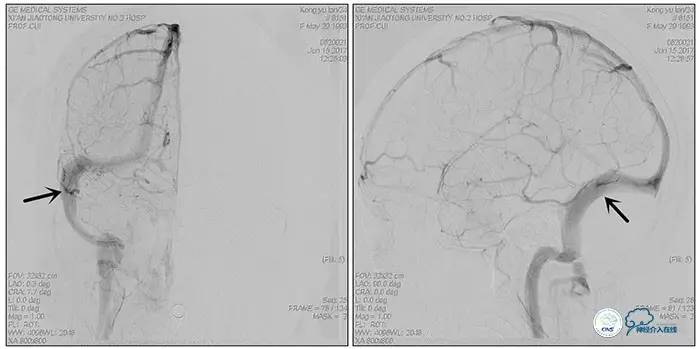

术中右侧ICA造影

右侧ICA斜位及窦内造影

右侧ICA斜位

窦内造影及路图

术中测压:

远端:520mmH2O,

近端:190mmH2O。

治疗方案:

1、8mm×40mm , EverCross球囊扩张;

2、8mm×40mm,Protégé自膨支架成形术。